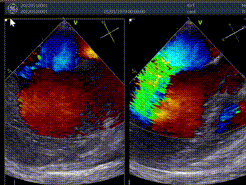

术前超声评估:

术前TEE提示重度功能性二尖瓣反流,反流位于A2/P2;

前瓣长度:25mm;后瓣长度:16mm;

前、后瓣叶对合深度:7.7mm;对合长度2.8mm;

瓣叶及瓣环无钙化,二尖瓣有效开口面积5.9cm²。

手术于全麻下进行,手术采用经典股静脉房间隔途径,房间隔穿刺后置入24F导引导管及二尖瓣夹输送系统,在TEE引导下准确植入一枚二尖瓣夹,瓣膜夹位置稳定,植入后反流下降至1+,二尖瓣跨瓣平均压力阶差3mmHg,双孔化形成,遂移除器械输送系统。患者术后恢复良好,瓣膜夹位置稳定,已于5月16日出院。此次手术得到了医院领导、超声科、心胸外科、麻醉科、体外循环组、重症医学科、医务科及杂交手术室等科室的大力支持。